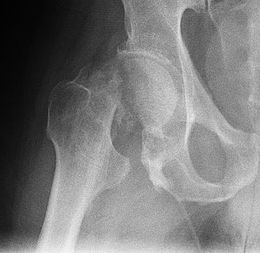

Le diagnostic est affirmé sur la radiographie du bassin et de la hanche qui montre la fracture et sa localisation